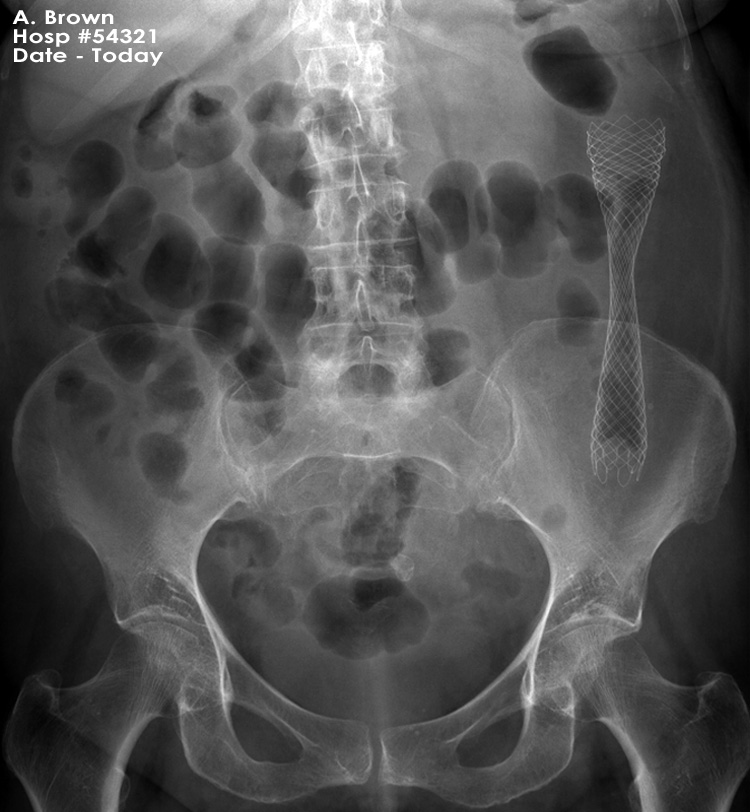

Abdominal X-ray - Scenario 1

- You requested a chest X-ray which was normal. Following a CT scan another radiological procedure was performed.

- What procedure has been performed?